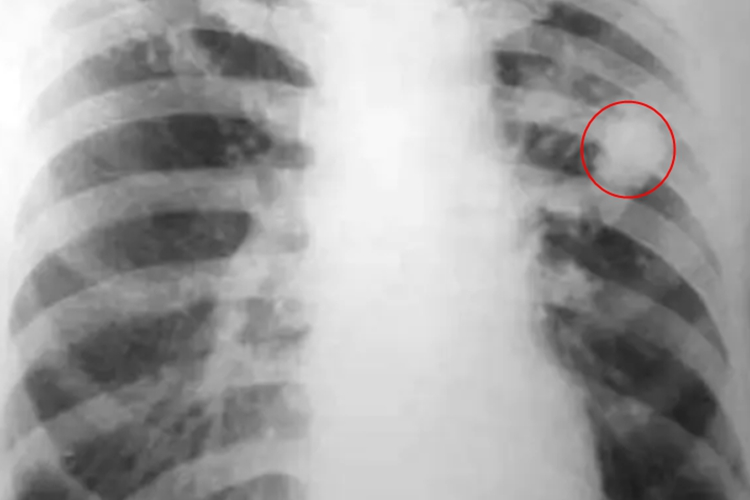

结核球:表现为球内有钙化灶或液化坏死形成空洞,同时有卫星灶,直径2-4cm,多小于3cm。